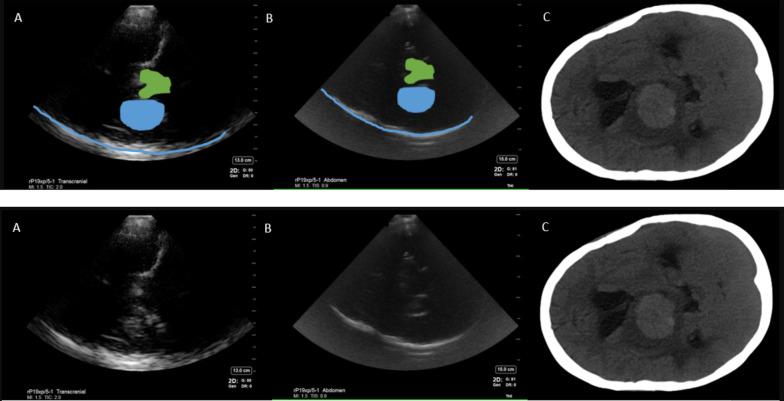

After obtaining IRB approval, a blinded investigator performed cranial ultrasound (Fujifilm, Sonosite Xporte, transcranial and abdominal presets) through temporal windows on 11 patients with intracerebral pathology within 72 h of last CT/MRI (computed tomography scan/magnetic resonance imaging) brain after being admitted to a neurocritical care unit in Aug 2020 and Nov 2020-Mar 2021. Images were then compared to patient's CT/MRI to inform topography. Inferential statistics were reported.

Mean age was 57 (28-77 years) and 6/11 were female. Six patients were diagnosed with ICH, 3 with ischemic stroke, 1 subarachnoid hemorrhage, and 1 brain tumor. The sensitivity and specificity of point of care diagnosis of ICH compared to CT/MRI brain was 100% and 50%, respectively. Mean time between ultrasound scan and CT/MRI was 13.3 h (21 min-39 h). Falx cerebri, choroid calcification and midbrain-related artifacts were the most reproducible hyperechoic signals. Abdominal preset on high gain yielded less artifact than Transcranial Doppler preset for cranial B mode imaging. False positive ICH diagnosis was attributed to intracerebral tumor and midbrain-related artifact.

平均年龄为57岁(28 - 77岁),11例中有6例为女性。6例患者被诊断为ICH,3例为缺血性卒中,1例为蛛网膜下腔出血,1例为脑肿瘤。与头颅CT/MRI相比,POCUS诊断ICH的敏感性和特异性分别为100%和50%。超声扫描与CT/MRI之间的平均时间为13.3小时(21分钟 - 39小时)。大脑镰、脉络丛钙化和中脑相关伪像是最可重复的高回声信号。对于头颅B模式成像,腹部预设在高增益时产生的伪像比经颅多普勒预设少。ICH诊断的假阳性归因于脑肿瘤和中脑相关伪像。